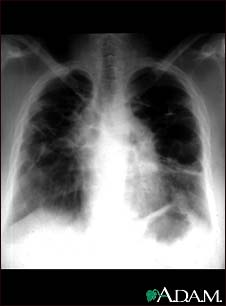

Sarcoid, stage IV - chest X-ray

This film shows advanced sarcoid, scarring of the lungs (the light streaking), and cavity formation (the dark areas in the upper right side of the picture).